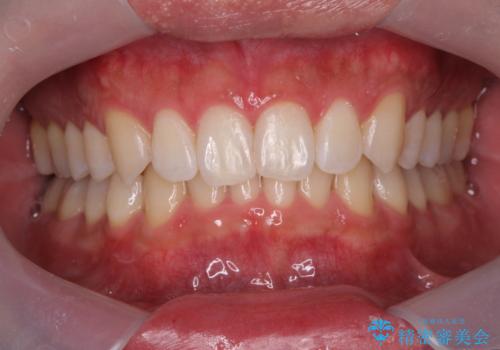

挙式を10日後に控えた患者様のホワイトニング施術をさせて頂きました。

違和感の無い白さにしたい…とのご要望があった為、施術中は患者様と白さ及び

知覚過敏の症状の有無を含め確認し慎重に進め患者様にも大変ご満足頂く事が出来ました。